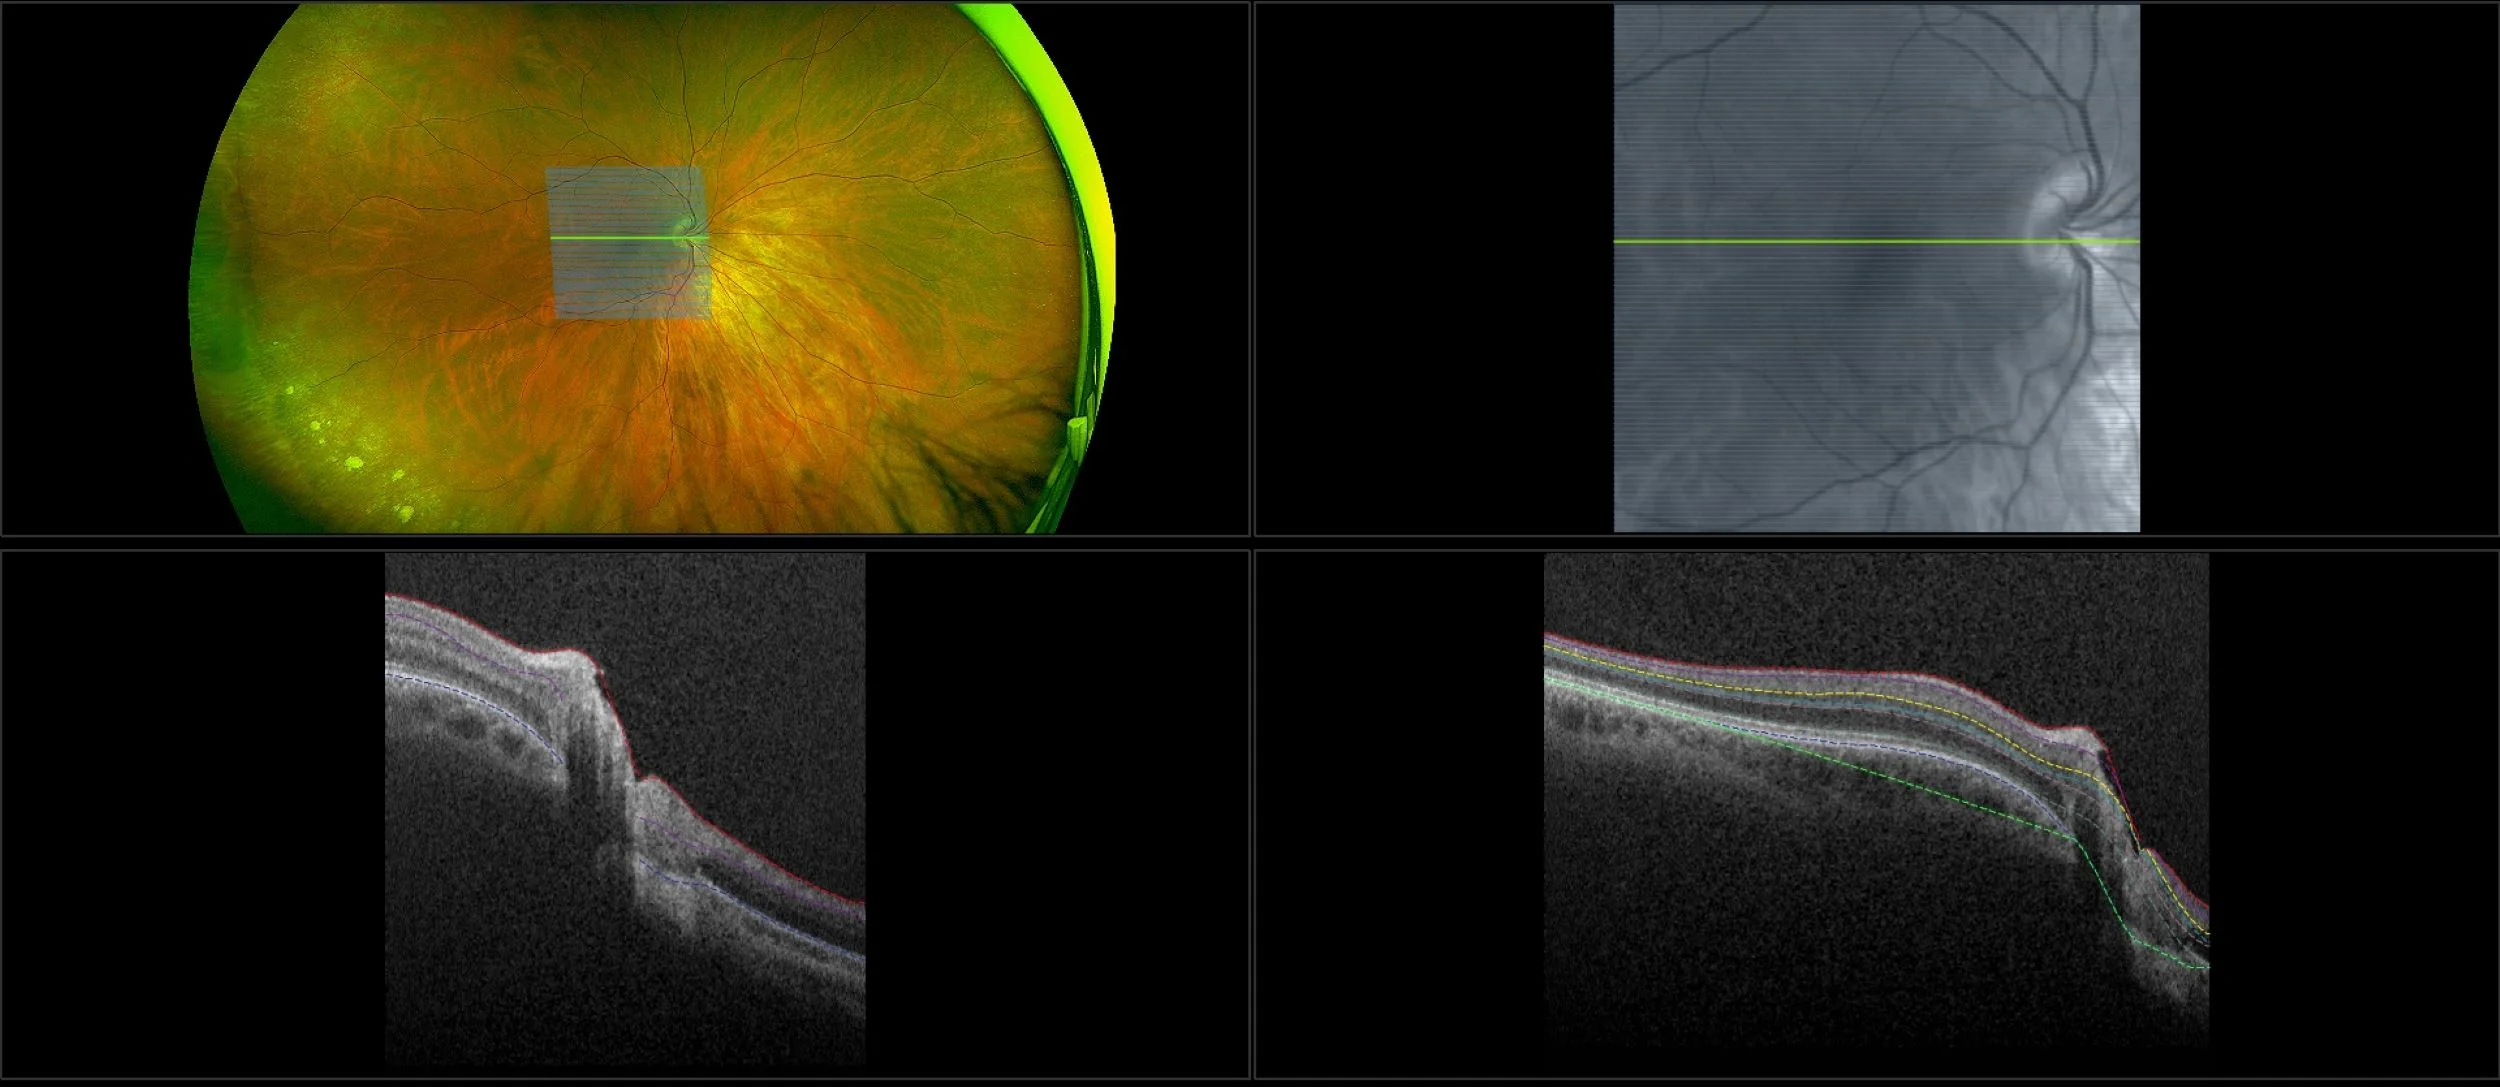

This material is designed as a searchable reference resource to support clinical decision-making. The information contained here should be used as general guidance when viewing optomap and OCT images from Optos devices. The differential diagnosis should be made under the direction of the responsible physician. These images were taken on the latest ultra-widefield optomap devices.

optomap Recognizing Pathology is searchable by pathology and/or optomap image modality. You may search by multiples of each selection. Each individual case is represented by the accompanying thumbnail image. Most cases include several different optomap image modalities. To view a full description of the case, please click on the thumbnail. Each image in the case will be made available through our OptosAdvance software which provides multi-dimensional visualization of digital images to aid in the analysis of anatomy and pathology. Support and pathology definitions can be found by selecting one of the buttons, above. Should you have questions, please complete the form below.